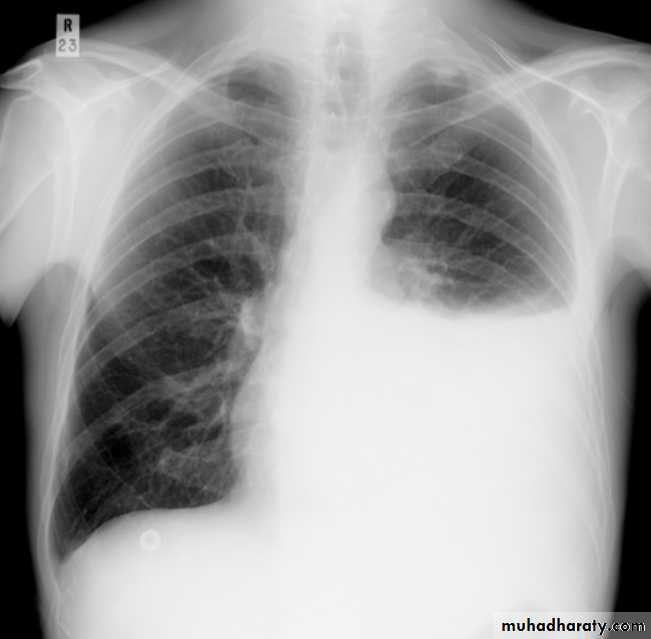

PneumothoraxPneumothorax refers to the presence of gas (air) in the pleural space. When this collection of gas is constantly enlarging with resulting compression of mediastinal structures it can be life-threatening and is known as a tension pneumothorax

Radiographic features

Chest radiograph

A pneumothorax is, when looked for, usually relatively easily appreciated. Typically they demonstrate:

visible visceral pleural edge see as a very thin, sharp white line

no lung markings are seen peripheral to this line

the peripheral space is radiolucent compared to adjacent lung

the lung may completely collapse

the mediastinum should not shift away from the pneumothorax unless a tension pneumothorax is present